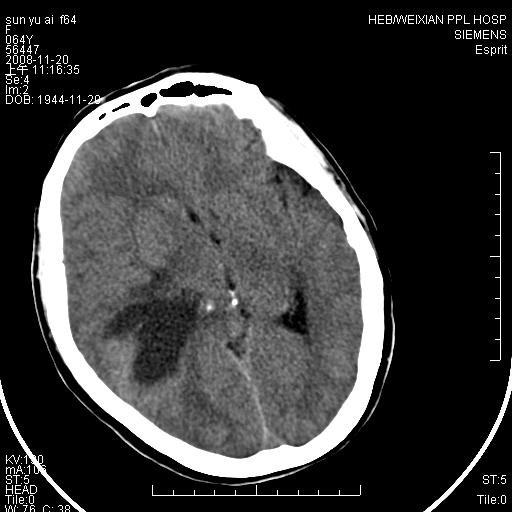

影像表现:侧脑室三角区附近可见以形态不规则的囊实性肿块,其中以囊性成分为主,实性成分为辅,边缘清晰,未见水肿,轻度占位效应,脉络丛钙化向内上移位,右侧脑室轻度扩大(也许体位所致),

1、右侧大脑半球囊实性占位病变,以囊性变为主,实性部分位于病变外后侧,周围无明显水肿,占位征象明显。

2、多考虑胶质瘤可能性大。

右颞顶叶囊实性占位,有壁结节。考虑间变性胶质瘤可能性大,建议增强进一步检查。

囊实性占位,实性部分为等密度或稍高密度,无明显水肿征考虑 -----脑膜瘤或室管膜瘤.其他待排,建议mri 增强检查

右颞顶叶囊实性占位,有壁结节,考虑胶质瘤可能性大,建议增强进一步检查。